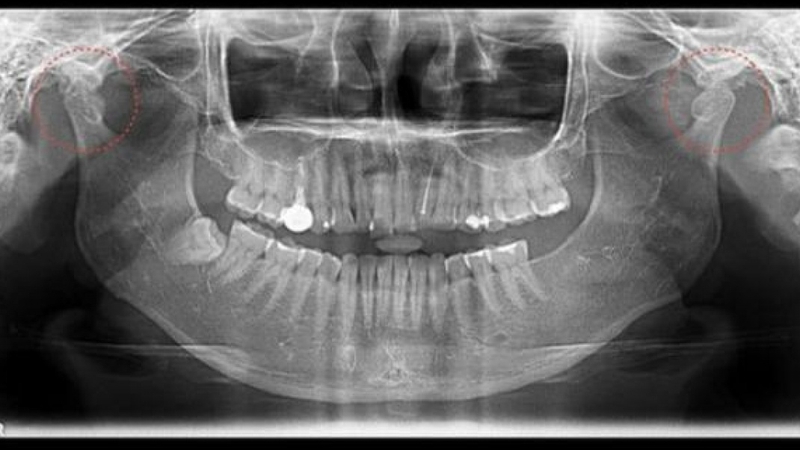

Với một số trường hợp khi mắc bệnh lý liên quan đến khớp thái dương hàm thì cần phải tiến hành chụp X quang. Thực tế, có nhiều phương pháp và kỹ thuật chẩn đoán bệnh lý viêm khớp thái dương hàm, nhưng chụp X quang vẫn là phương pháp được ưu tiên bởi mức độ quan trọng và chính xác.

Mục đích của chụp X quang khớp thái dương hàm là để khảo sát khớp thái dương hàm, hỗ trợ chẩn đoán các bệnh lý về răng hàm mặt. Khi đó, bác sĩ có thể thực hiện chụp X quang răng chuẩn ngang đầu, chụp X quang theo mặt phẳng ngang hầu, X quang từ phía dưới cằm lên đến đỉnh đầu, X quang sọ mặt từ xa.